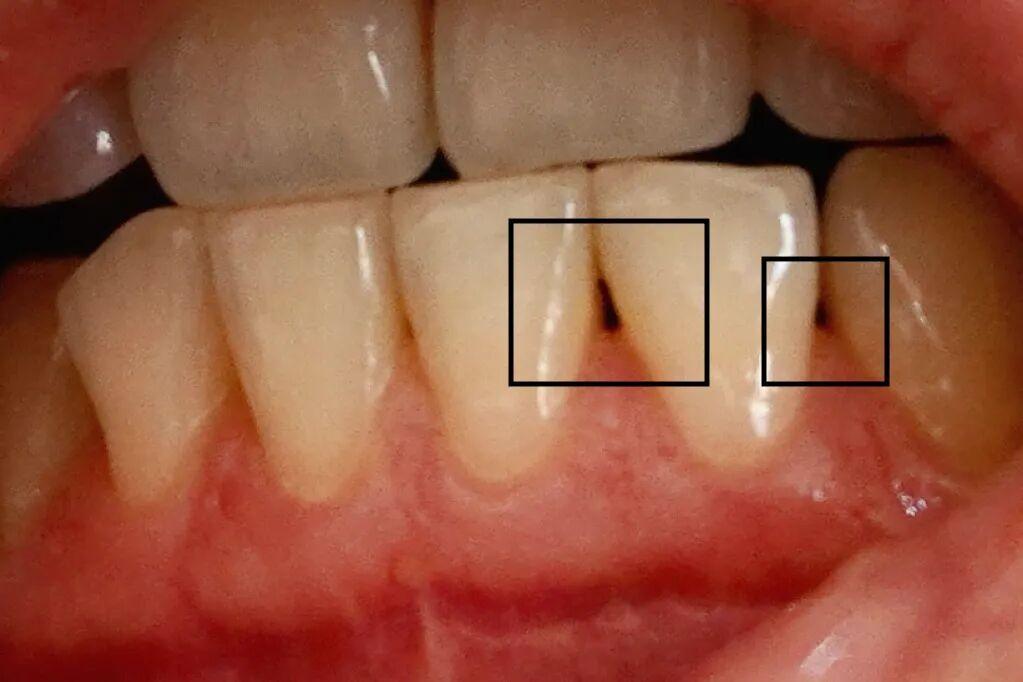

主要表現爲牙與牙之間空出了一個「黑三角」、牙根外露得越來越嚴重、牙齦變薄、牙縫看起來也寬了不少——真·喝涼水都塞牙!

圖爲牙結石

圖片來源:站酷海洛

輕則出現冷熱酸敏感等症狀[7],重則還可能導致菌斑滯留、根面齲、牙髓炎[8]

不同於普通「牙冠齲」,發生在牙釉質

「根面齲」一般發生在牙根

牙齦退縮、牙根裸露缺乏保護,細菌往上啃洞

左爲牙冠齲,右爲根面齲